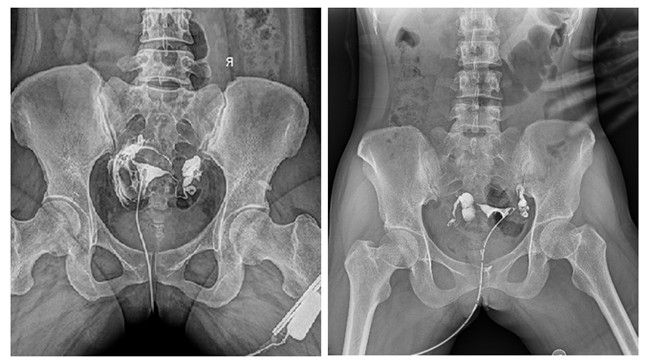

相較于傳統胃腸機,動態DR矩形采集面積大,一次曝光即可顯示整個盆腔,大幅減少觀察時間,可控的瞬時照射避免受檢者吸收過多的X線,對育齡期女性的檢查尤為重要。毫秒級時間內高清點片,可以在造影劑流動的過程中完成拍片,抓拍到關鍵圖像,更加清楚地了解到管腔的具體通暢情況及堵塞部位,對檢查及診斷有非常重要的價值。

此外,應用平板動態DR進行子宮輸卵管造影,還可以在加壓推注下,使部分輸卵管輕、中度堵塞的患者得以通暢,起到一定的治療作用。